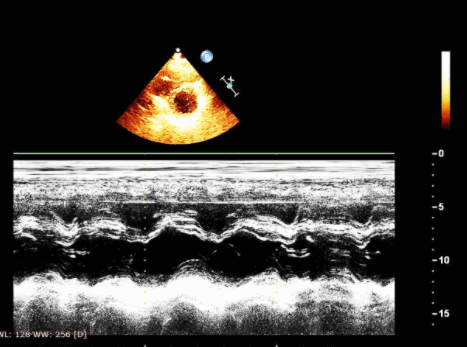

М-режим и двумерная эхокардиография: морфология правого сердца. Лучшие подходы для изучения правых отделов

- Парастернальная позиция ЭхоКГ по длинной и короткой осям, а также апикальные и подреберные четырехкамерные изображения.

- ЧПЭхоКГ из трансгастральной позиции с видом на длинную ось и короткую ось правого желудочка (ПЖ) и средне-пищеводный четырехкамерный вид.

Хроническая ЛГ приводит к расширению оттока правого желудочка и легочной артерии (ЛА) (> 3 см). При хронической ЛГ средней тяжести М-режим клапана легочной артерии показывает срединно-систолическое закрытие и потерю нормальной волны А в 30-60% случаев. При стенозе легочного клапана волна А увеличивается, а срединно-систолическое закрытие клапана отсутствует. При остром легочном сердце из-за эмболии в легочные сосуды правый желудочек и толщина его свободной стенки обычно нормальны, но наблюдается общее снижение сократимости. В этом случае могут быть видны правожелудочковые или правые предсердные тромбы.